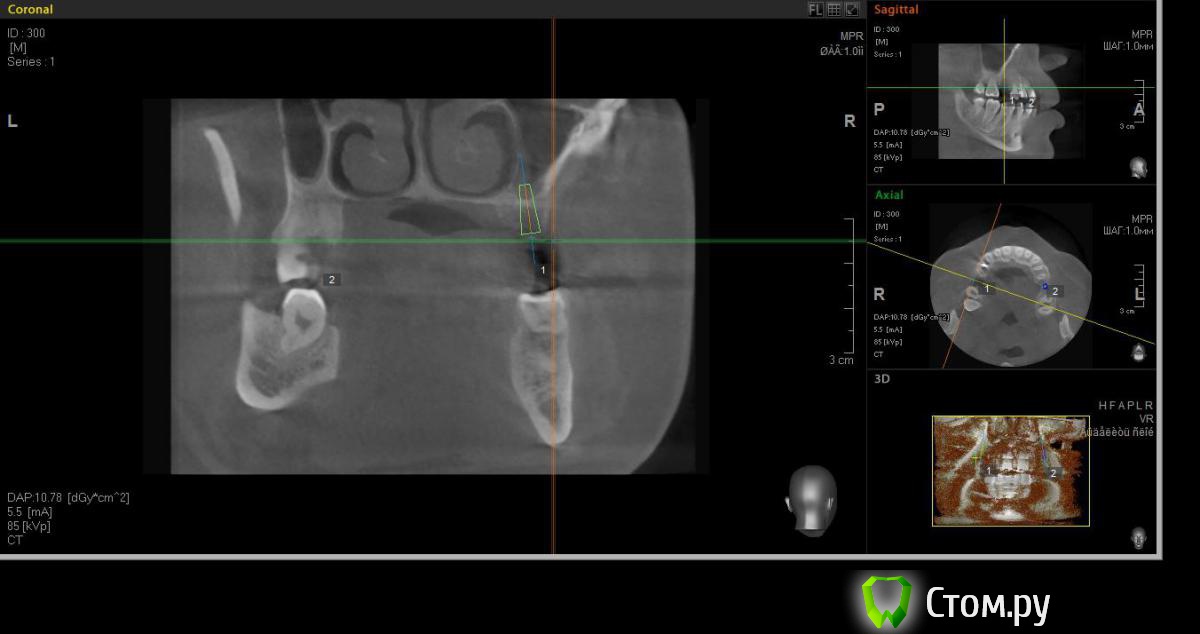

faity Опубликовано 18 мая, 2014 Автор Поделиться Опубликовано 18 мая, 2014 хочу вот так сделать, на 1.6 мягкий лифт, в обл 2.6 не лезтьвинты Ankylos 1.6- 4,5/11 2.6- 3,5/9,5кости в области 1.6- 7,5мм, должно хватить для закрытого, открытый пациент не потянет по финансам.какие мысли? Ссылка на комментарий

red_butler Опубликовано 19 мая, 2014 Поделиться Опубликовано 19 мая, 2014 Я бы не планировал хирургию исходя из финансовых пожеланий пациента, и 1.6 вел бы с открытым синусом. Представьте что при закрытом порвали мембрану, открытый придется делать, и за свой счет. Винт в позицию 1.6 поставил бы меньшего диаметра Ссылка на комментарий

faity Опубликовано 19 мая, 2014 Автор Поделиться Опубликовано 19 мая, 2014 значит буду открытый делать, и винт на 3,5а по поводу 2.6 предложений никаких? Ссылка на комментарий

faity Опубликовано 19 мая, 2014 Автор Поделиться Опубликовано 19 мая, 2014 Я бы не планировал хирургию исходя из финансовых пожеланий пациента, и 1.6 вел бы с открытым синусом. Представьте что при закрытом порвали мембрану, открытый придется делать, и за свой счет. Винт в позицию 1.6 поставил бы меньшего диаметрапоменял винты на 3,5/11 Ссылка на комментарий

red_butler Опубликовано 19 мая, 2014 Поделиться Опубликовано 19 мая, 2014 (изменено) Не знаю диаметры винтов в этой системе, между 3.5 и 4.5 Промежуточного нет?А 2.6 без синуса и диаметр больше Изменено 19 мая, 2014 пользователем red_butler Ссылка на комментарий

faity Опубликовано 19 мая, 2014 Автор Поделиться Опубликовано 19 мая, 2014 Не знаю диаметры винтов в этой системе, между 3.5 и 4.5 Промежуточного нет?А 2.6 без синуса и диаметр большепромежуточных к сожалению нета 2,6 больше не получитсяэто при ныненшнем радиусе и положении, если делать больше винт, то больше углублять, а тогда в синус провалюсь Ссылка на комментарий